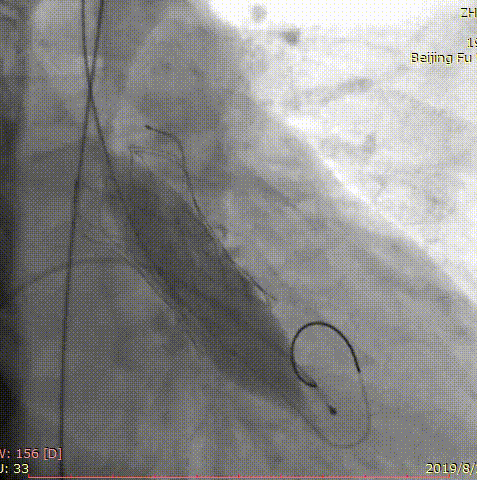

第三位患者是一位84岁女性,因间断头晕伴气短2年,加重1年入院,超声心动图提示主动脉瓣重度狭窄,左室壁肥厚,节段性室壁运动减低,主动脉瓣平均跨瓣压差91mmHg,收缩期流速 m/s,瓣口面积 0.6cm2。患者合并房颤、慢性肾功能不全、贫血。完善CT检查,测得主动脉瓣环 21*25mm,周长71.3mm,面积399.2mm2,患者三叶瓣,钙化分布较均匀,结合瓣上多平面分析方法,选择经左侧股动脉,应用微创心通 20*40mm敖广球囊预扩张,并成功植入Vitaflow 24mm主动脉瓣膜。术后超声提示收缩期流速1.7m/s,较术前明显下降。

术前影像